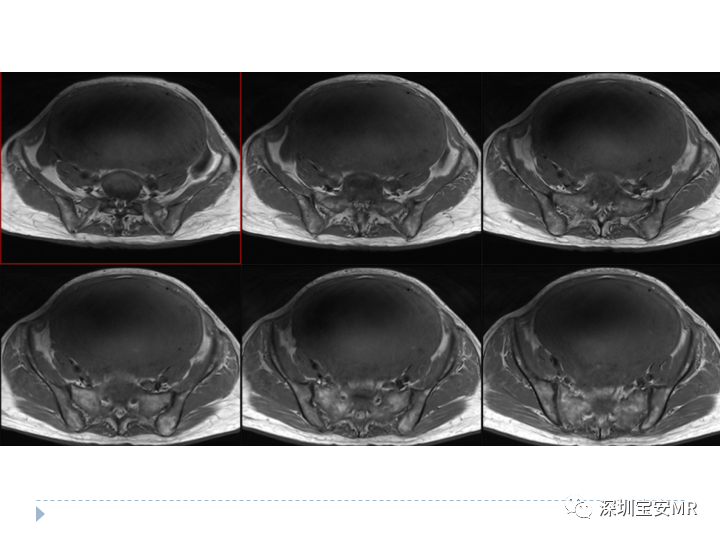

子宫内膜间质肉瘤1例MR影像